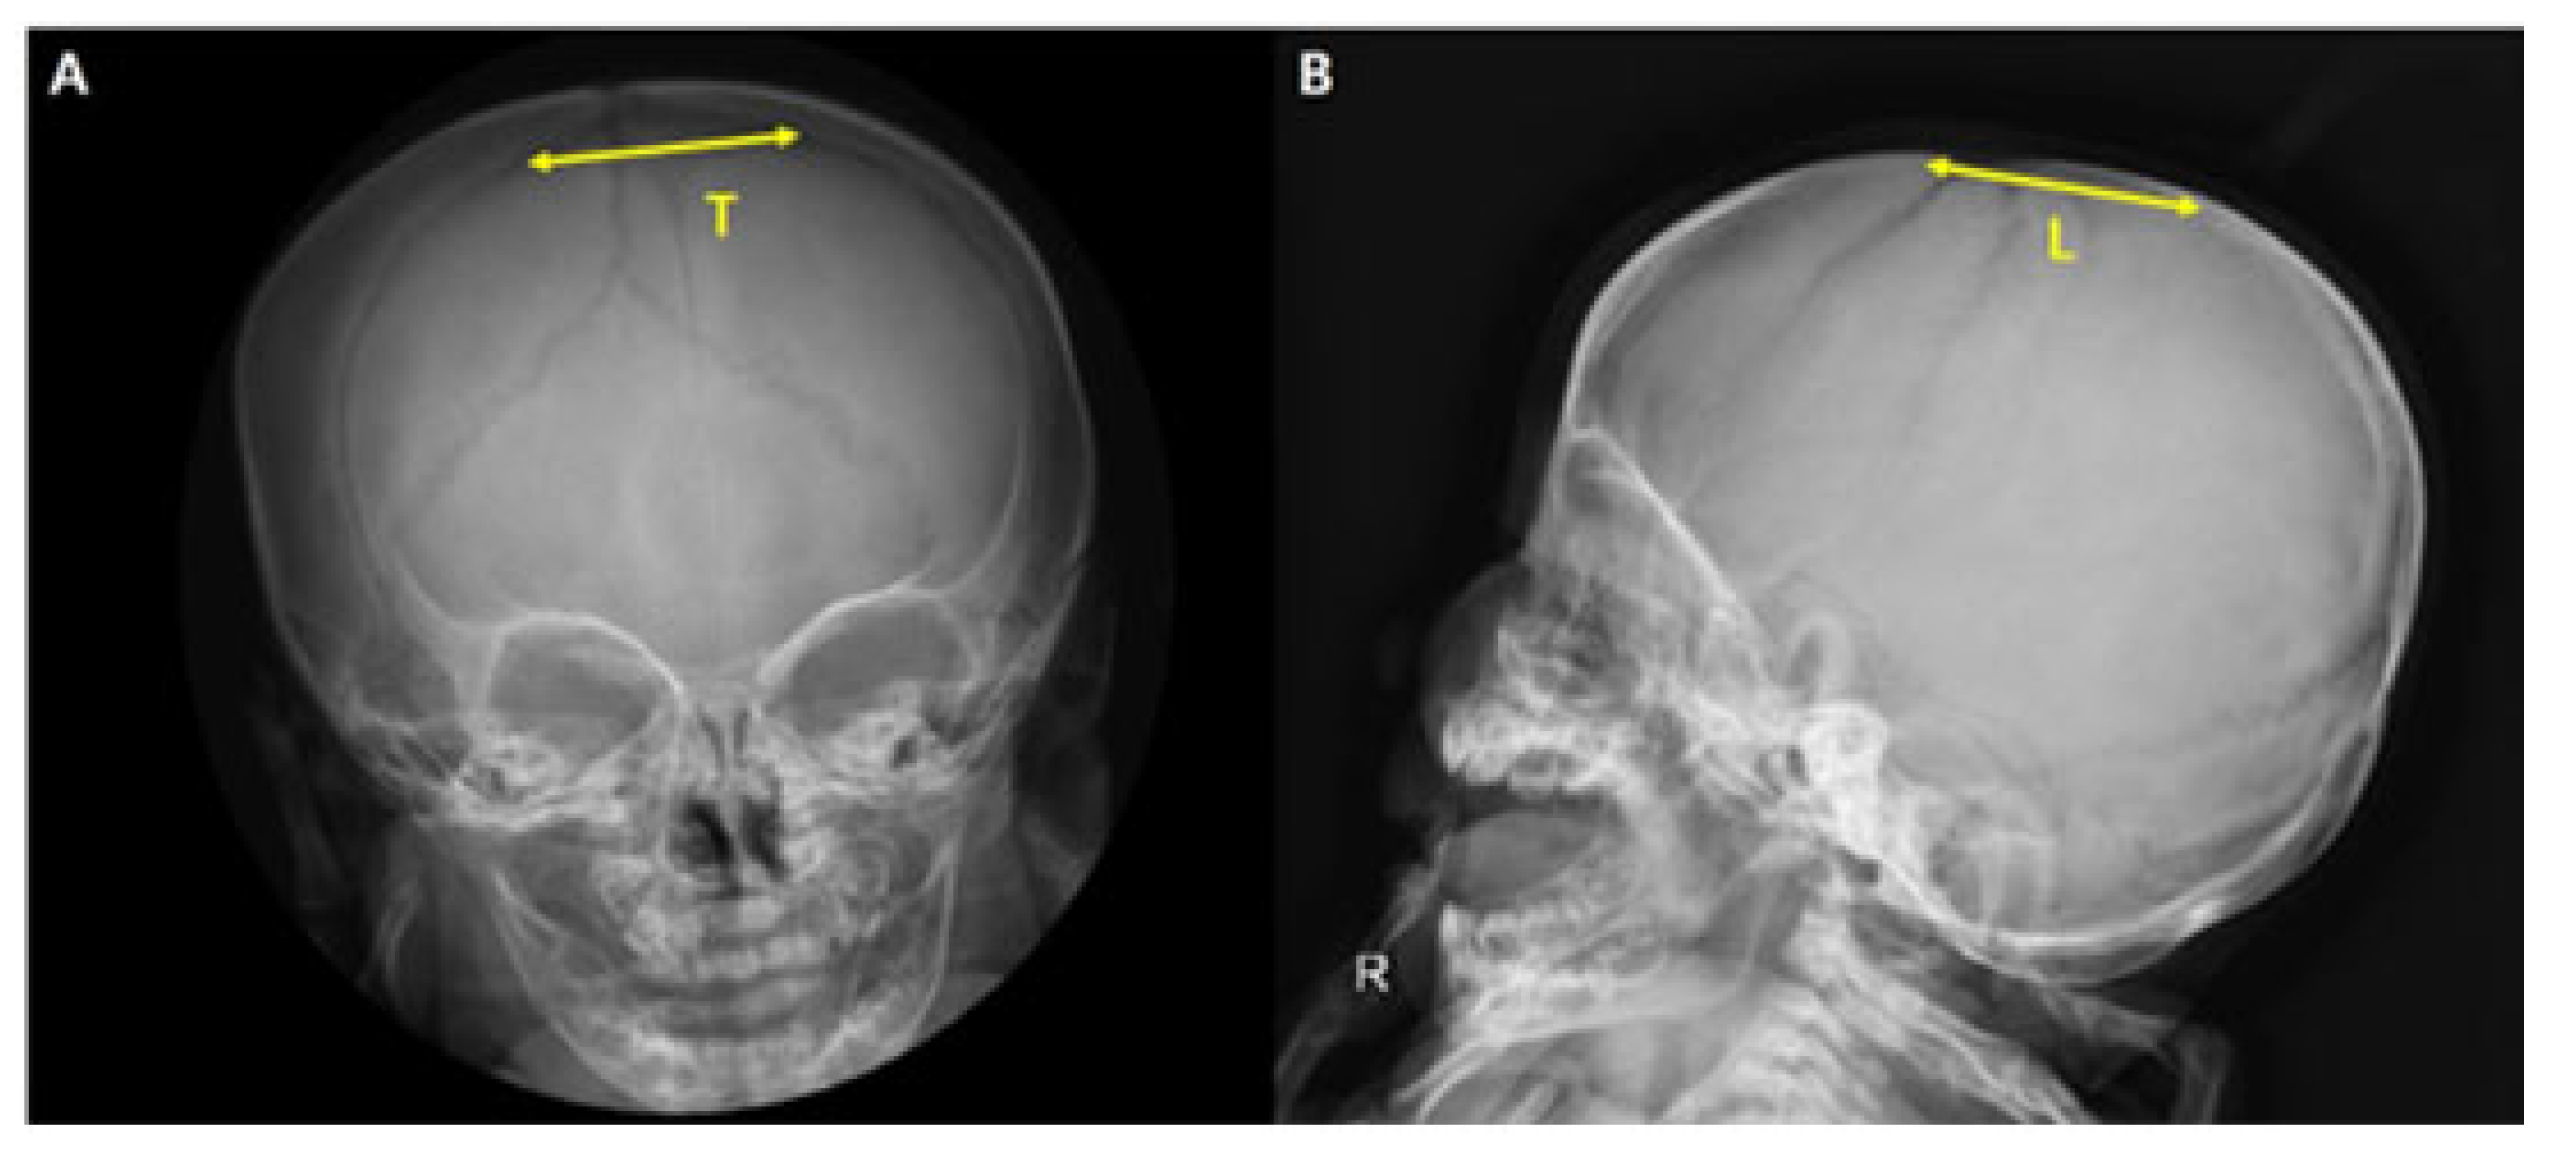

2.3. Measurements